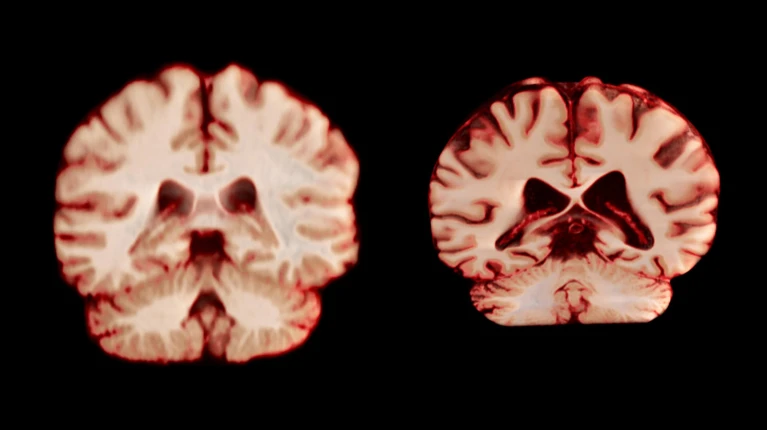

健康大脑(左)和受阿尔茨海默病影响的大脑。

这款名为“区域液体管理的策略性精确注入”(SPIRAL)的植入物,是一种轻薄柔软的导管,可在脑内多个位点精准释放药物。它不仅能够覆盖更广泛、更复杂的脑组织区域,同时保持了植入物的小型化与微创特性。

研究团队表示,神经系统疾病往往起源于大脑特定区域,而现有工具难以精准靶向这些区域。SPIRAL实现了在不增加额外风险的前提下,同时对多个脑区进行药物干预,有望革新此类疾病的治疗模式。